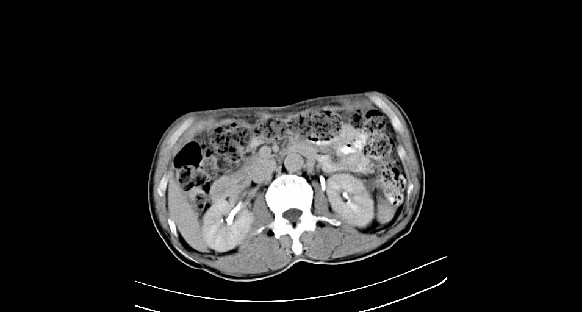

男性,70岁,体检b超发现左肾占位,请各位战友发表一下观点

左肾有两个病灶,且较大的病灶内可见点状钙化灶,增强扫描边缘也是呈渐进性强化,中央部分未见明显强化